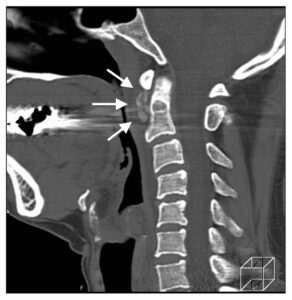

咽後膿瘍と鑑別を要した石灰沈着性頸長筋腱炎の3例臨床雑誌整形外科 63巻3号医書.jp。

咽後膿瘍が疑われた急性石灰沈着性頸長筋腱炎の1例臨牀透析 34巻9号医書.jp。

頸部痛+嚥下時痛」謎解きに有効な検査と治療 3ページ目 :日経メディカル。

発熱を伴う急性の頸部痛 もう騙されない!外来に現れるミミック疾患 16– 日本医事新報社。

感染症との鑑別が困難な石灰沈着性頸長筋腱炎 - 医療法人信岡会 菊池中央病院。